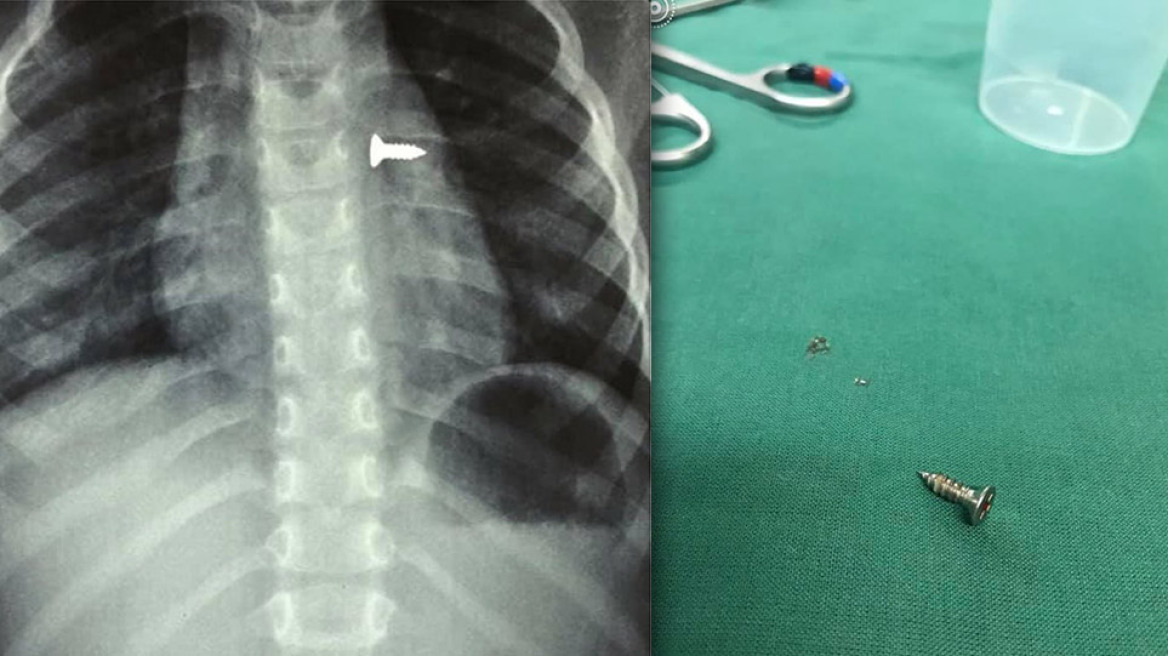

Σοκάρουν οι ακτινογραφίες από ένα κοριτσάκι στην Κρήτη που κατάπιε βίδα, η οποία κατέληξε στον αριστερό του πνεύμονα.

Σύμφωνα με τα όσα έκανε γνωστά ο αναπληρωτής καθηγητής ΩΡΛ της Ιατρικής Σχολής Κρήτης, Μανώλης Προκοπάκης, την Τρίτη μεταφέρθηκε σε νοσοκομείο του Ηρακλείου ένα τρίχρονο κορίτσι το οποίο κατάπιε μία βίδα.

Αμέσως έβγαλε ακτινογραφίες, που έδειξαν πως η βίδα βρισκόταν στον αριστερό του πνεύμονα.

Οι γιατροί οδήγησαν το κορίτσι στο χειρουργείο και μετά από αρκετή ώρα κατάφεραν να αφαιρέσουν την βίδα.

Ο κ. Προκοπάκης σε ανάρτησή του στα social media ανέφερε: «Πολύ επείγον χειρουργείο! Πριν από λίγο. Αφαίρεση βίδας από αριστερό βρογχικό δέντρο τρίχρονου κοριτσιού. Πολύ επικίνδυνο…».